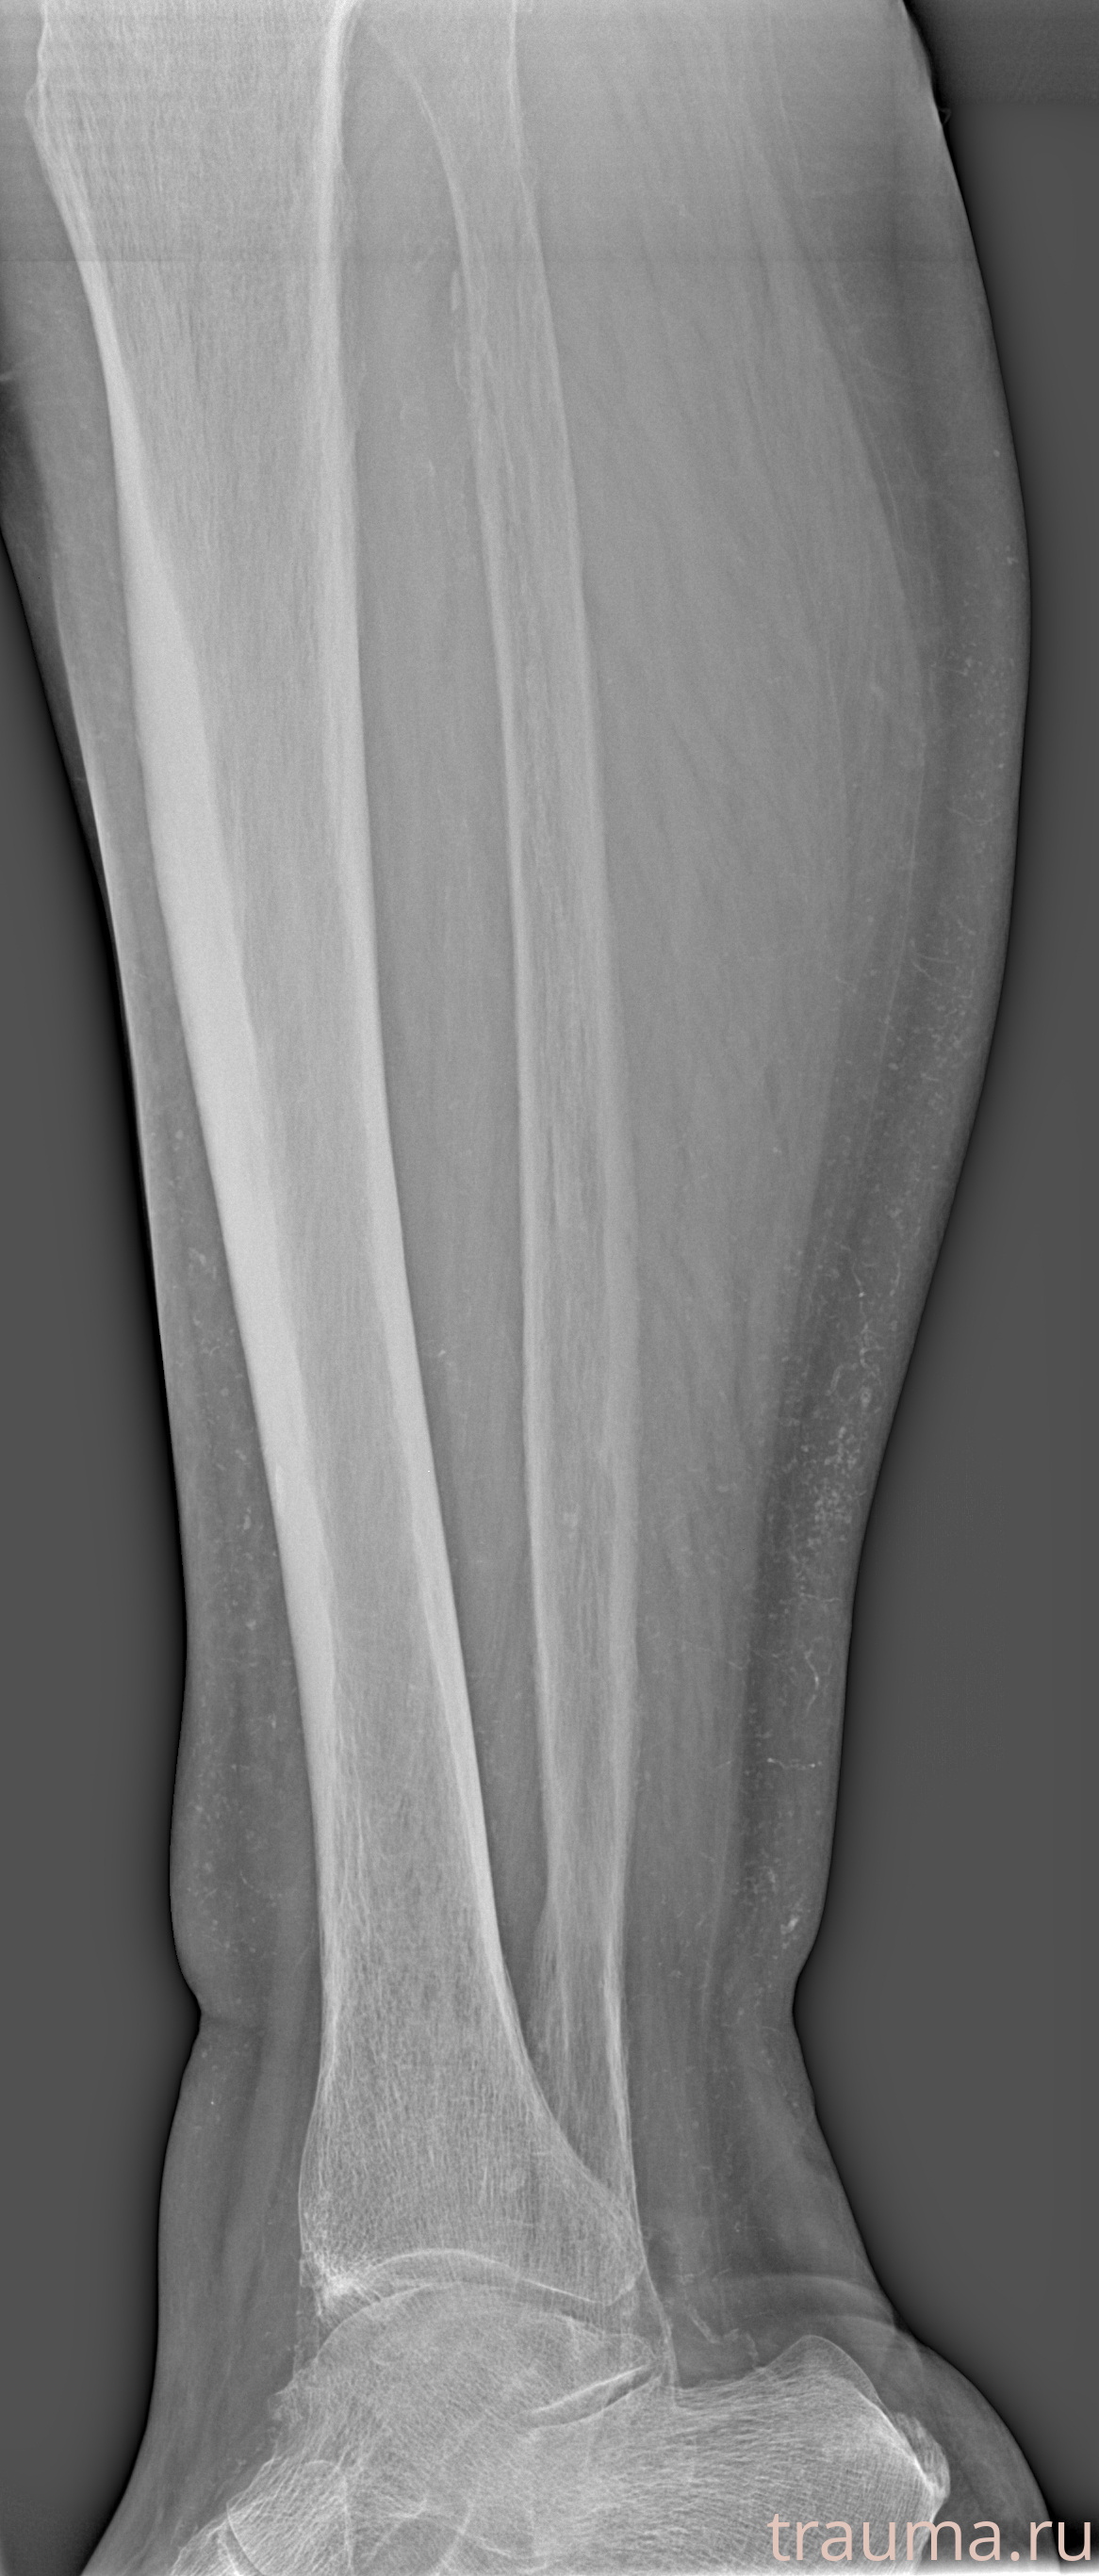

Рентгенограммы

Рентген на дому: по вашему адресу приезжает врач-рентгенолог, травматолог-ортопед с мобильным рентгеновским аппаратом, проводит диагностику травмы или заболевания, делает необходимые рентгенограммы, дает рекомендации по дальнейшему лечению. Получить качественные снимки в домашних условиях возможно благодаря уникальной методике, разработанной МосРентген Центром для института  Склифосовского